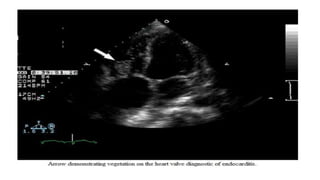

Large oscillating intracardiac mass suggestive

of infective etiology

Large oscillating intracardiacmass suggestive of infective etiology

VEGETATION DEFINITION

• a valvular vegetation is defined as "a discrete mass of echogenic

material adherent at some point to a leaflet surface and distinct in

character from the remainder of the leaflet" based upon the following

characteristics

• Texture – Gray scale and reflectance of myocardium

●Location – Upstream side of the valve in the path of the jet or on

prosthetic material

●Characteristic motion – Chaotic; independent of valve motion

●Shape – Lobulated and amorphous

●Accompanying abnormalities – Abscess and pseudoaneurysm,

fistulae, prosthetic dehiscence, paravalvular leak, significant

preexisting or new regurgitation

• Vegetations also characteristically prolapse into the upstream

chamber

• Vegetations tend to flank the regurgitant jet